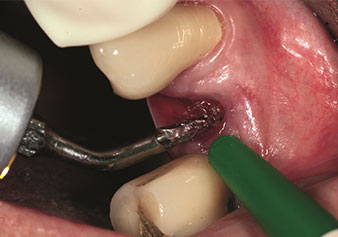

One application, which is often underestimated is the atraumatic extraction of tooth roots or root fragments in the scope of alveolar management. The fine periotomes, which are currently available in two versions (EX1 and EX2 from W&H), can also be used to remove teeth which have previously undergone special endodontic treatment or ankylosed roots with ease. This results in extraction alveoli where both the hard and soft tissue are fully intact as it is generally possible to avoid reflection.

This establishes the optimal basis for subsequent or immediate implant treatment (Figures 1 and 2 included with the kind permission of Dr Torsten Conrad, Bingen a. Rhein).

Fine periotome (EX1 instrument)

Fig. 1: Fine periotome (EX1 instrument).

Photo: © Dr Torsten Conrad (Bingen a. Rhein)